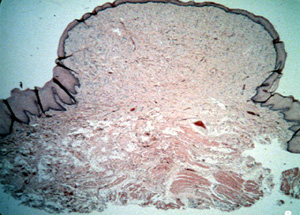

A  una mayor resolución que la imagen anterior, el crecimiento muestra  colágeno sumamente engrosado alrededor de un vaso sanguíneo.  Los fibroblastos en forma de  husos están  esparcidos y no hay inflamación. Si éste fuera un verdadero fibroma  uno esperaría ver muchas células y mucho menos colágeno. Aunque la prognosis es excelente, puede haber repetición si los factores irritantes locales permanecen .